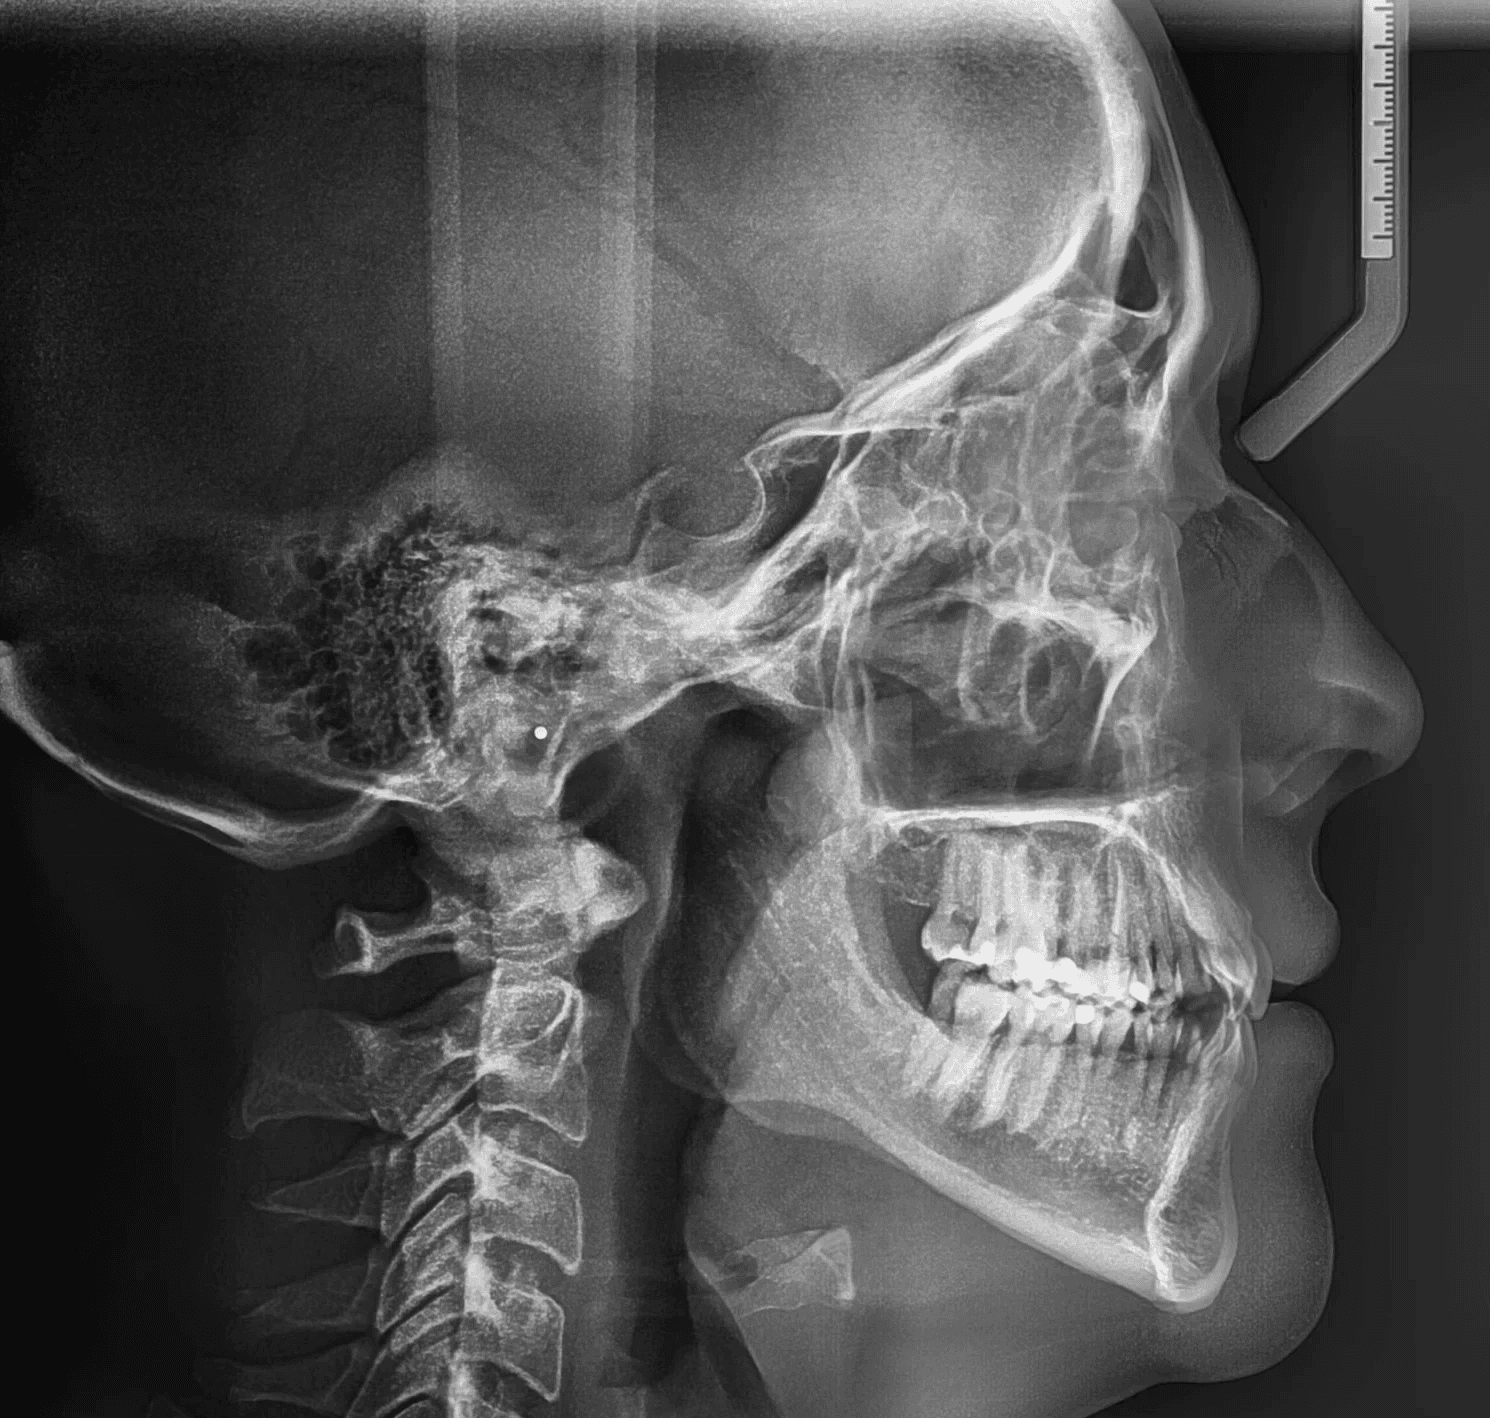

Initial treatment

X-RAYS